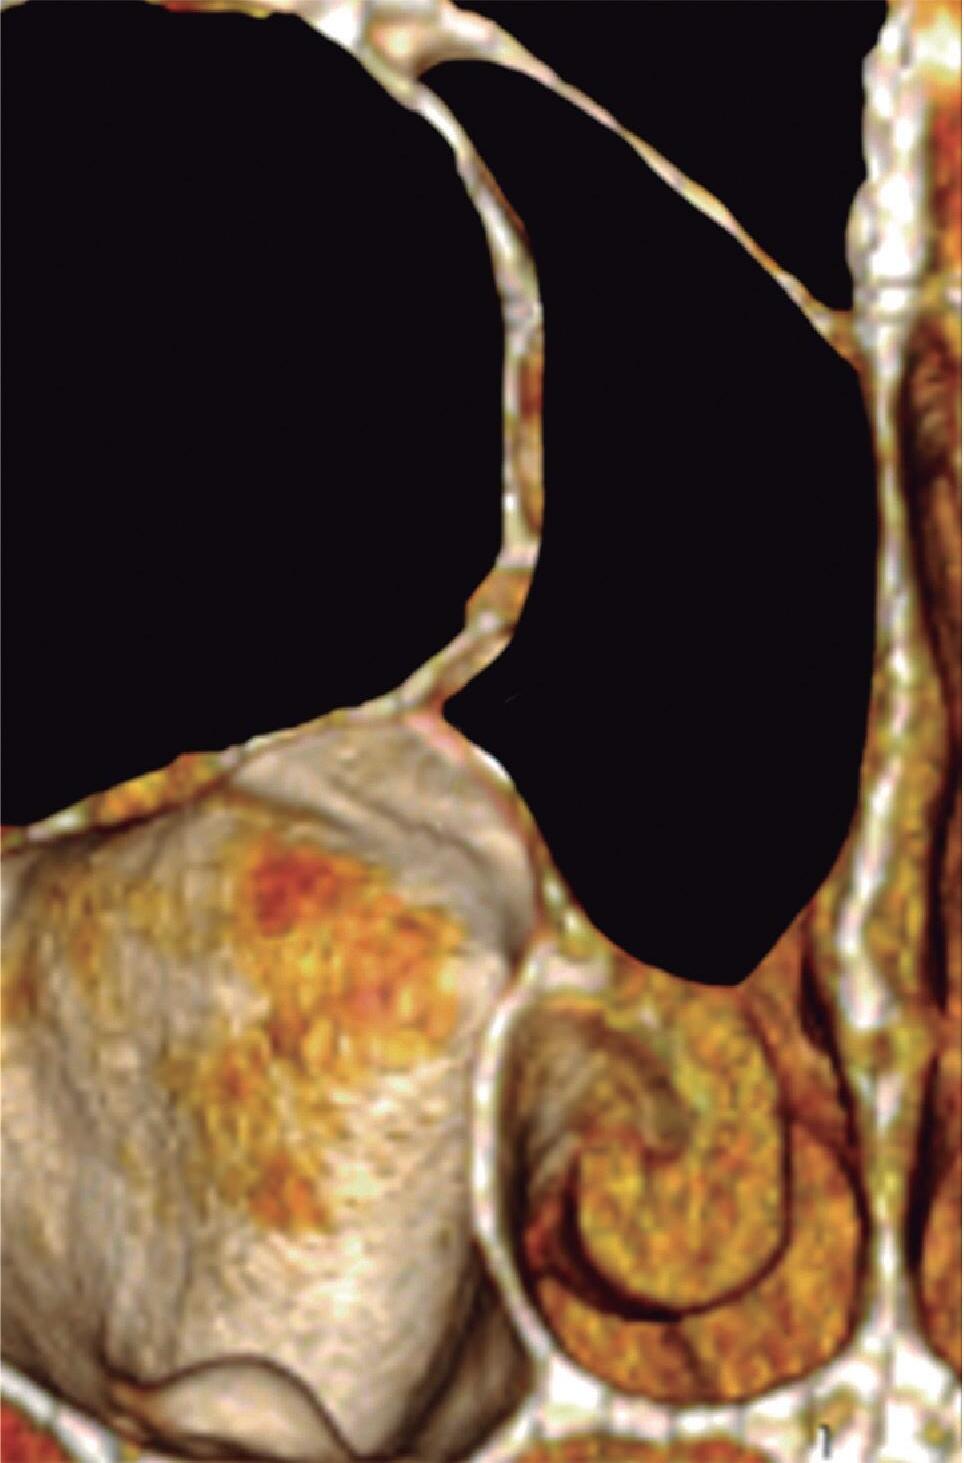

1-7. TC com reconstrução 3D mostrando em vermelho apenas o seio etmoidal e não o osso etmoidal, e sua relação com a fossa nasal, o seio maxilar, órbita e fossa anterior.

1-8. Osso etmoidal e seio etmoidal (amarelo) observar o aspecto incompleto do teto do seio etmoidal que será coberto pelo osso frontal (rosa).